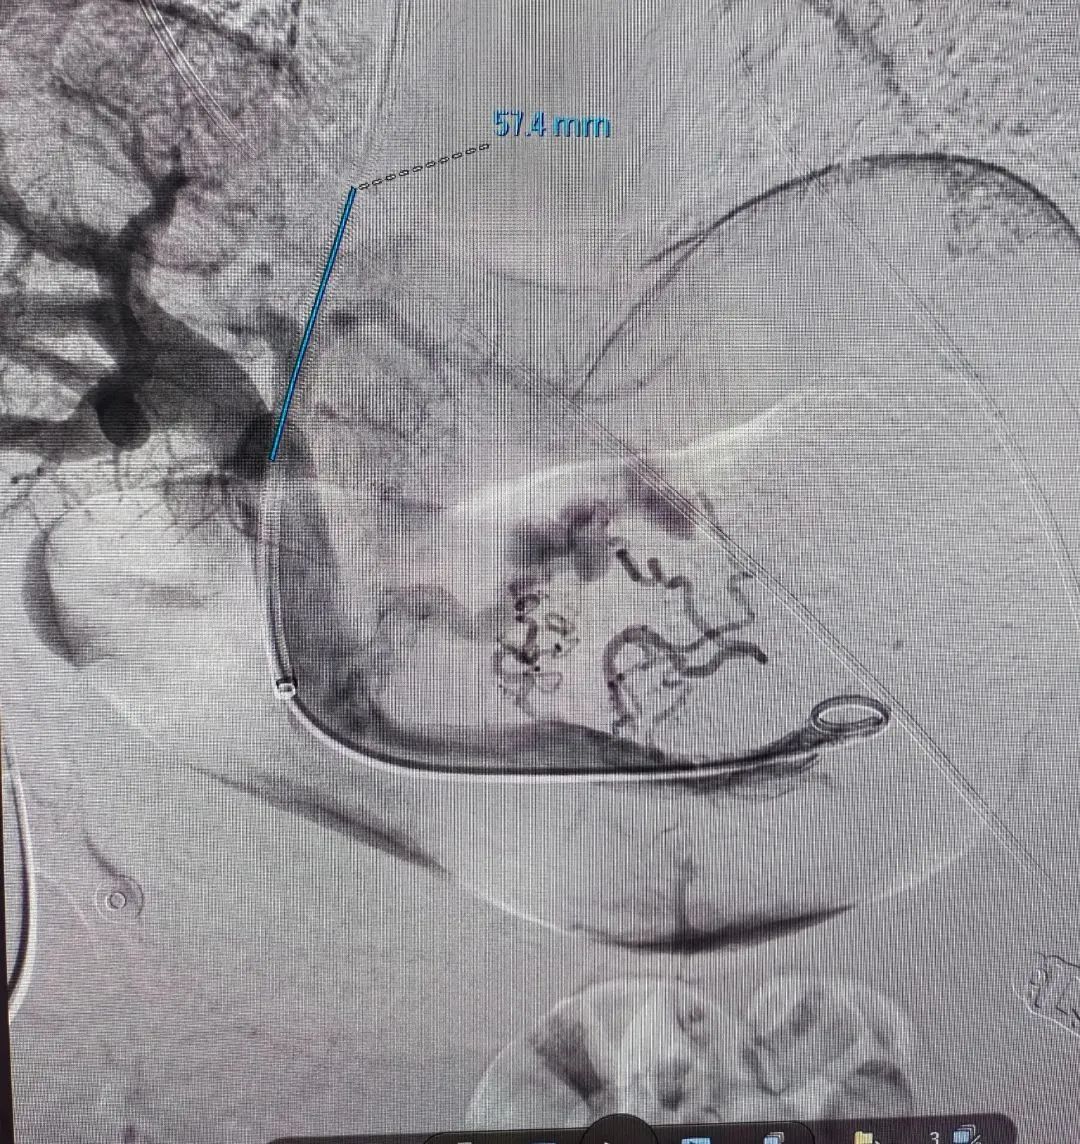

患者甘某某,男性,70岁,是一名乙型肝炎肝硬化患者,患者反复多次呕血,病情紧急,取得家属同意后,肝病科主治医师在科室人员的配合下,熟练进行门静脉穿刺、曲张食管-胃底静脉栓塞、门静脉球囊扩张以及支架植入术等一系列专业操作,约1个半小时,手术顺利完成,患者转回肝病专科进一步治疗后,好转出院。

经颈静脉肝内门体分流术(TIPS)被业内誉为“外周介入的技术高峰”,是借助介入器材,利用外科分流术的基本原理,达到治疗和预防食管-胃底静脉曲张破裂出血和顽固性胸腹水等门静脉高压并发症的一种治疗方法,对于急性消化道出血的高风险肝硬化患者来说,早期应用TIPS可以提高患者的生存率,降低再出血的发生率。